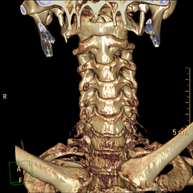

Prueba radiológica que consiste en obtener imágenes del hueso peñasco del temporal (oído interno, medio y externo) de alta definición anatómica mediante el empleo de un equipo de TC (Tomografía Computarizada). Indicaciones: pérdida de audición súbita o crónica, cuadros vertiginosos, mareo, malformaciones congénitas. - Angio – TC Troncos Supraaórticos

Prueba radiológica que consiste en obtener imágenes de las arterias carótidas del cuello de alta definición anatómica mediante el empleo de un equipo de TC (Tomografía Computarizada) y la inyección de contraste intravenoso. Posteriormente, las imágenes son reconstruidas en tres dimensiones (3D). Indicaciones: accidente vascular cerebral agudo, accidente vascular transitorio, soplo carotídeo. - TC Columna cervical

Prueba radiológica que consiste en obtener imágenes de las vertebras cervicales de alta definición anatómica mediante el empleo de un equipo de TC (Tomografía Computarizada). Indicaciones: cervicalgia sin/con irradiación a brazos, traumatismo.